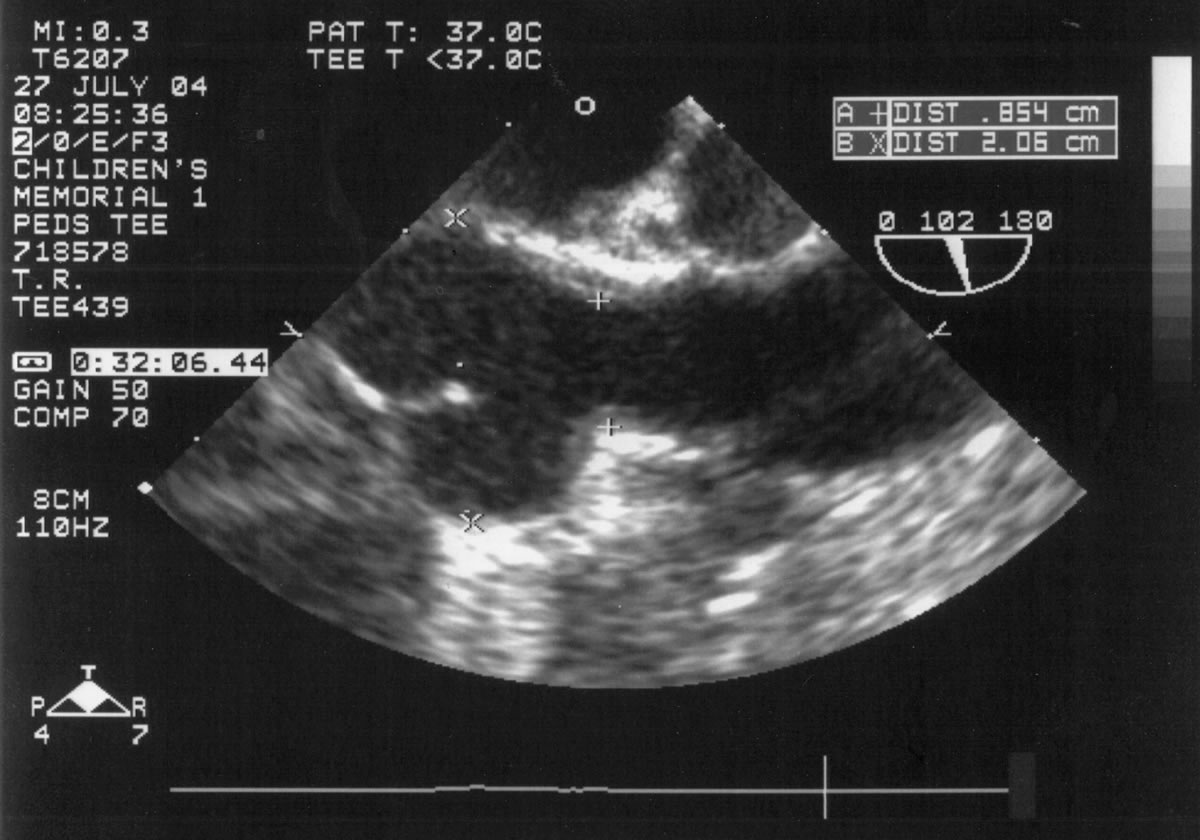

An asymptomatic, 5-year-old, 18-kg boy known by genetic testing to have Williams syndrome on physical examination had a IV/VI harsh systolic ejection murmur and no diastolic murmur.  Preoperative echocardiogram showed an aortic root dimension of 2 cm and the dimension at the level of stenosis in the ascending aorta was 8 mm.  Peak echocardiogram gradient was 70 mm Hg with a cardiac catheterization gradient of 50 mm Hg.  The child had no peripheral pulmonary artery stenosis.

Preoperative transesophageal echocardiogram in long-axis view shows ascending aorta with aortic valve to the left. The markers indicate the aoritc root dimension to be 2.0 cm and hte mid portion of the stenosis to be 0.8 cm.